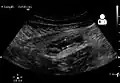

Abdominal ultrasonography, preferably with doppler sonography, is useful to detect appendicitis, especially in children. Ultrasound can show the free fluid collection in the right iliac fossa, along with a visible appendix with increased blood flow when using color Doppler, and noncompressibility of the appendix, as it is essentially a walled-off abscess. Other secondary sonographic signs of acute appendicitis include the presence of echogenic mesenteric fat surrounding the appendix and the acoustic shadowing of an appendicolith.[59] In some cases (approximately 5%),[60] ultrasonography of the iliac fossa does not reveal any abnormalities despite the presence of appendicitis. This false-negative finding is especially true of early appendicitis before the appendix has become significantly distended. Also, false-negative findings are more common in adults where larger amounts of fat and bowel gas make visualizing the appendix technically difficult. Despite these limitations, sonographic imaging with experienced hands can often distinguish between appendicitis and other diseases with similar symptoms. Some of these conditions include inflammation of lymph nodes near the appendix or pain originating from other pelvic organs such as the ovaries or Fallopian tubes. Ultrasounds may be either done by the radiology department or by the emergency physician.[61]

Ultrasound showing appendicitis and an appendicolith.[62]

Ultrasound showing appendicitis and an appendicolith.[62] -

Ultrasound of a normal appendix for comparison. -

A normal appendix without and with compression. Absence of compressibility indicates appendicitis.[59]